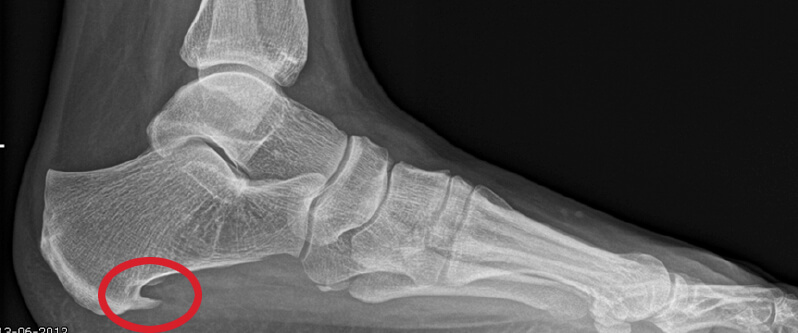

Een hielspoor is een botuitwas (verkalking) aan de onderzijde van het hielbot, het zogenoemde calcaneus. Deze verkalking bevindt zich op de plaats waar de peesplaat onder de voet, de fascia plantaris, aanhecht. Een hielspoor is goed zichtbaar op röntgenfoto’s en kan ook met echografisch onderzoek worden vastgesteld.

Hielspoor op röntgenfoto

Hielspoor duidelijk zichtbaar op deze op röntgenfoto.